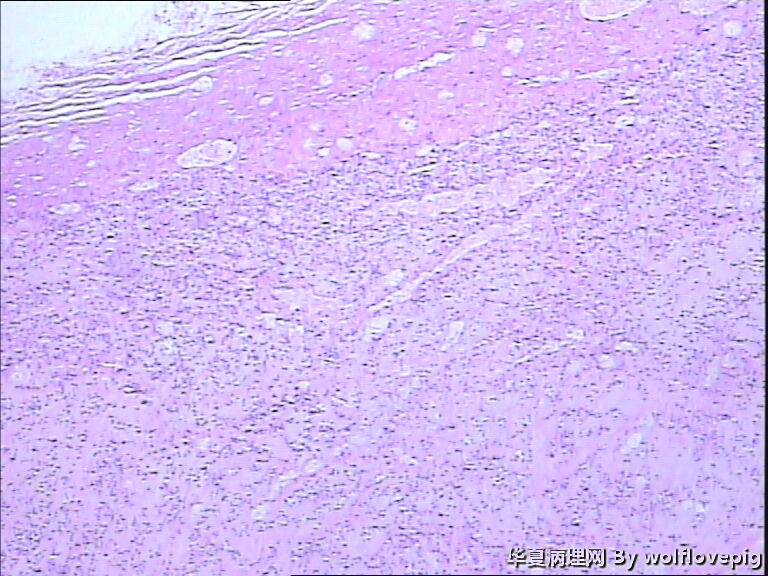

求助!肌瘤变性?

图3